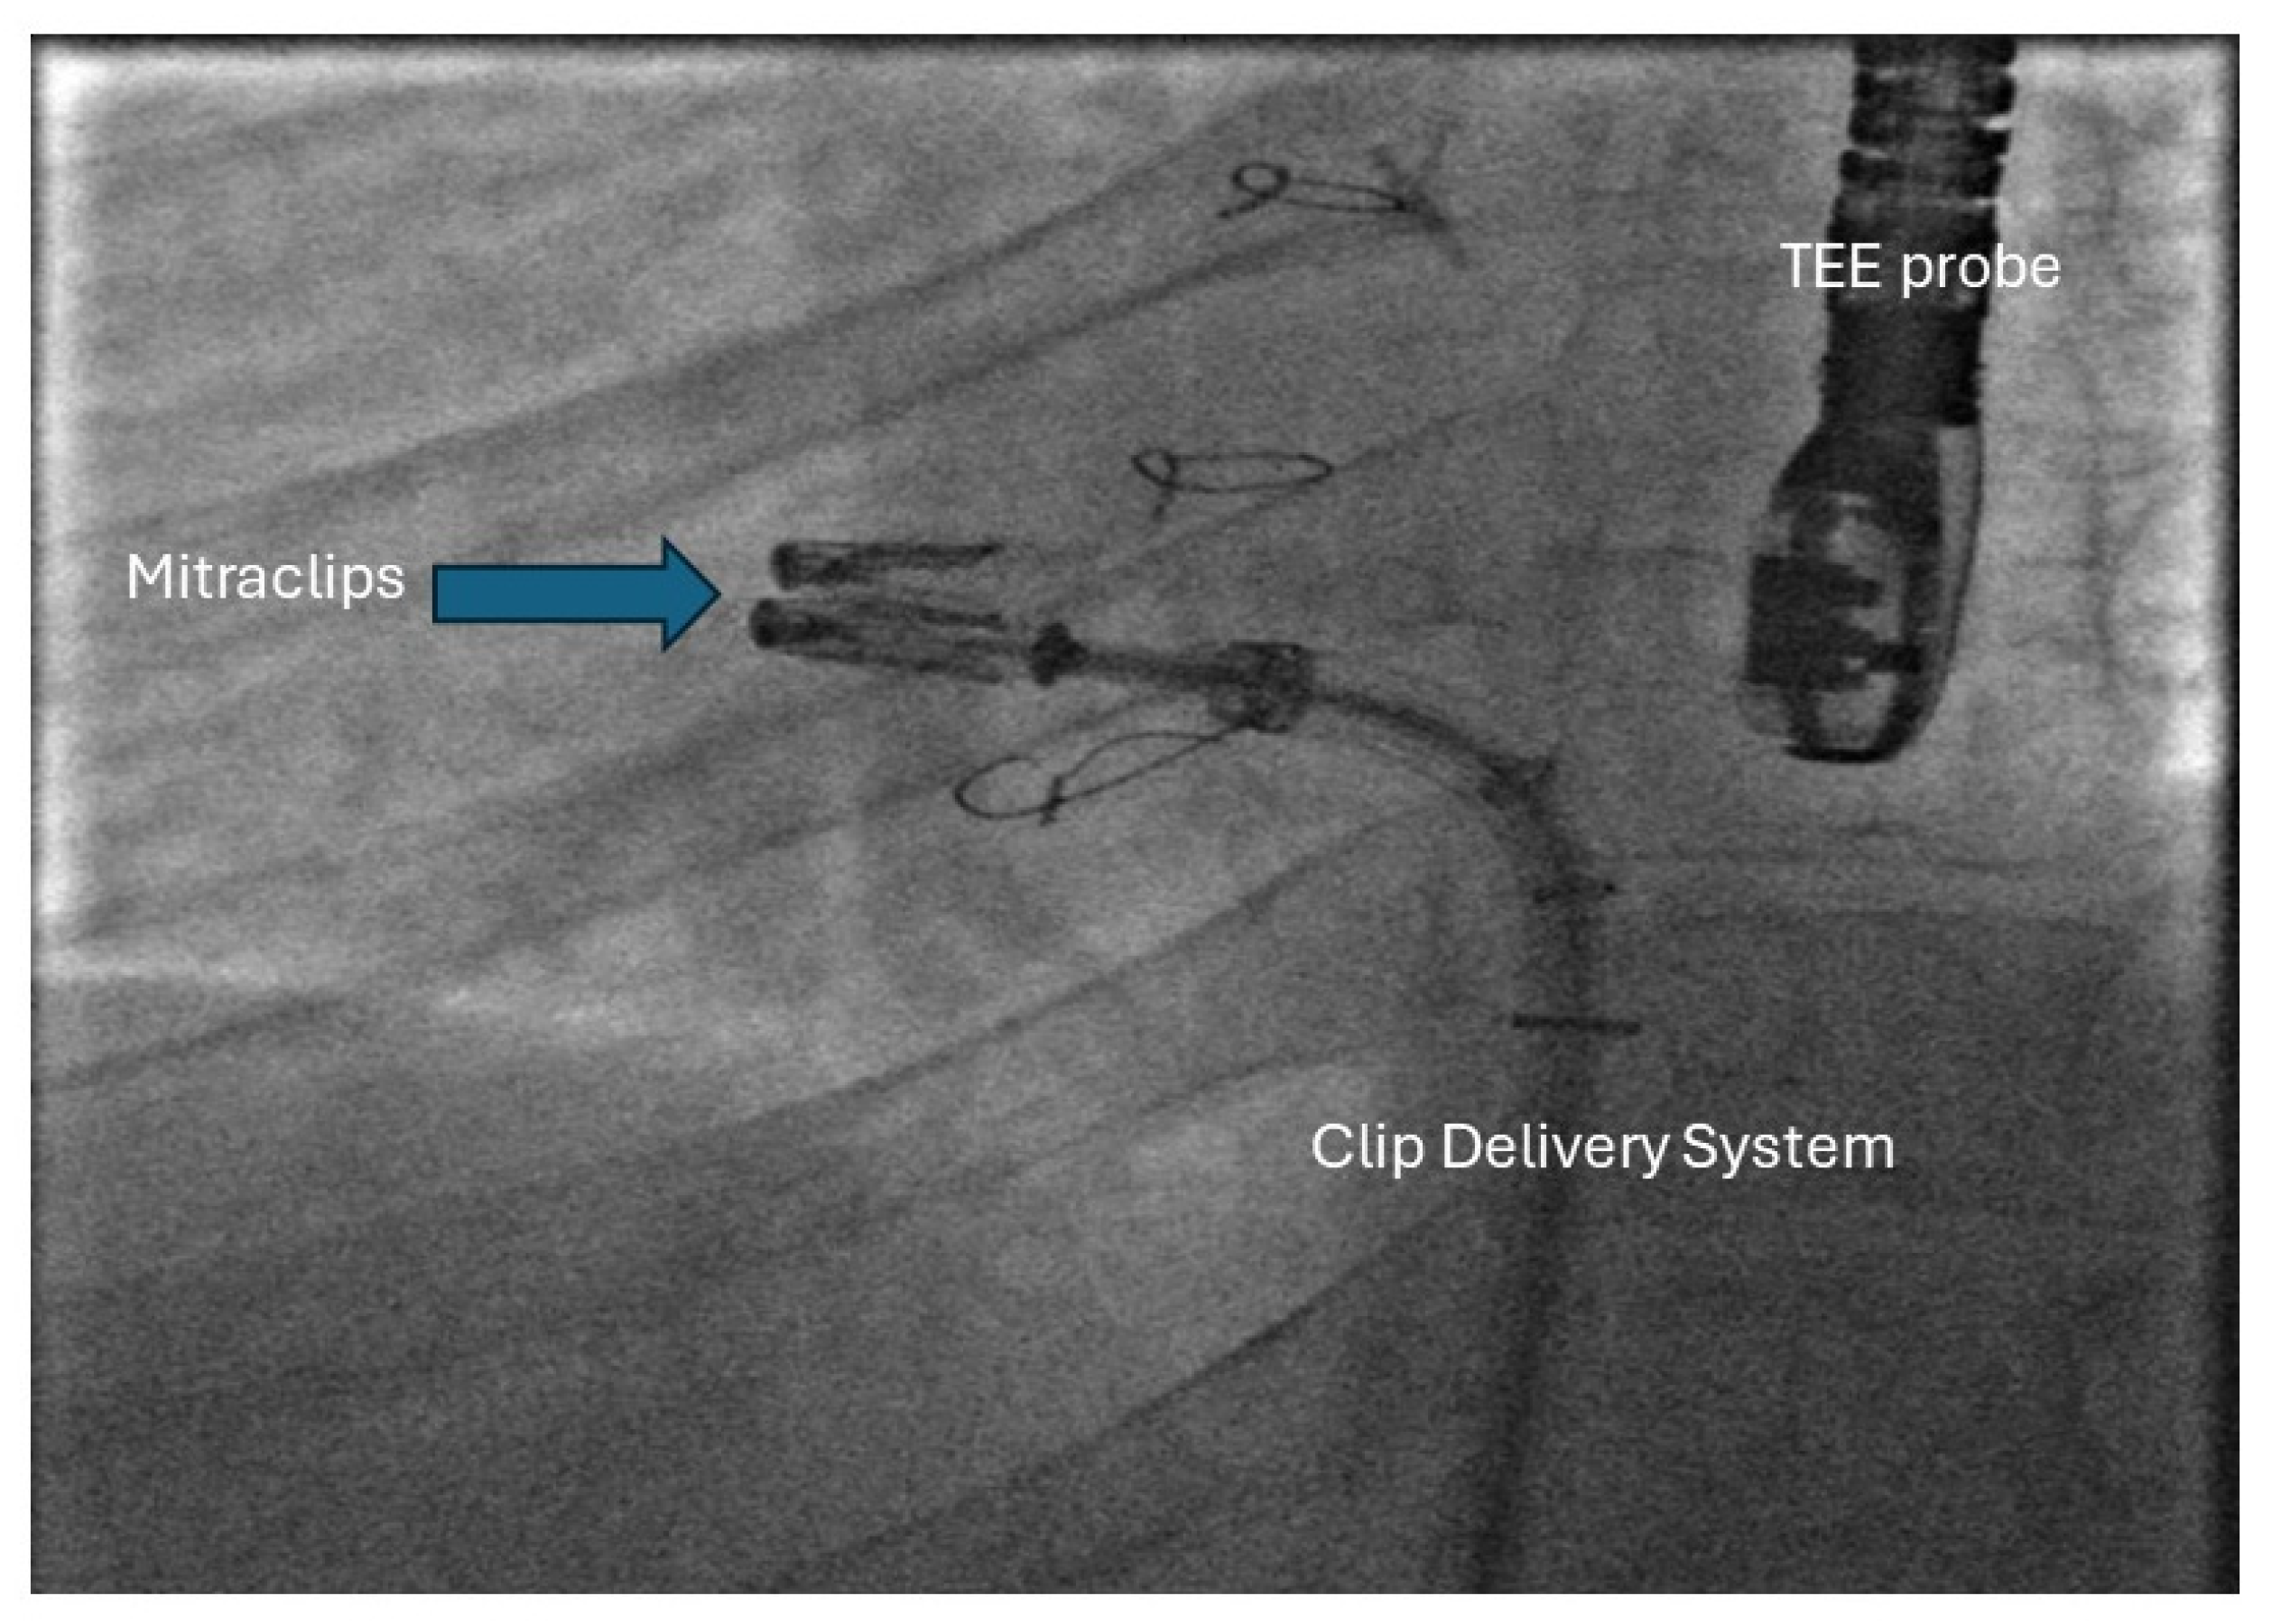

29. Percutaneous Intervention for AV Valve Regurgitation

- Kumar, P.; Gordon, B.M.; Kheiwa, A.; Abudayyeh, I. A case report of percutaneous MitraClip implantation in an adult with a double-outlet right ventricle. Eur. Heart J. Case Rep. 2023, 7, ytad247. [Google Scholar] [CrossRef] [PubMed]